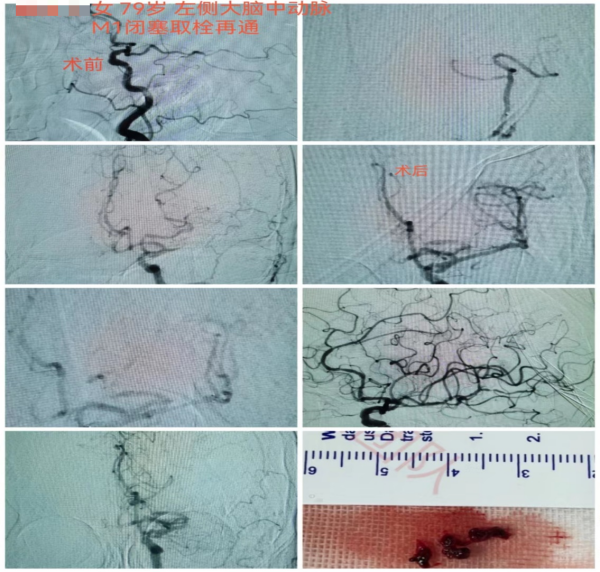

案例二:

8月19日上午6时左右,家住天心区79岁的蒋奶奶因四肢乏力在客厅摔倒,家属扶起后症状未见好转,且无法言语。

9时左右,家属将蒋奶奶送至长沙市融城医院,行头部CT和MRI后考虑左侧大脑中动脉闭塞引起的脑梗死,需立即接受动脉取栓治疗。长沙市融城医院立即联动我院高级卒中中心,启动卒中绿色通道。

12时24分,“120”救护车到达我院急诊,立即完善头颅CTA提示左侧大脑中动脉M1段栓塞。监测生命体征以及复查必要检查项目后,神经内科副主任医师冯铁桥与患者家属沟通病情及手术相关事项,签字后患者被转入早已做好准备的介入导管室,行“左侧大脑中动脉闭塞急诊介入开通术”,施行动脉取栓。

12时45分,患者被推进介入导管室,此时患者仍处于颅内大血管闭塞动脉取栓的黄金时间窗内(6小时),救治工作紧张有序地展开。10分钟后股动脉穿刺成功,患者的取栓血管通路顺利建立。

13时33分,患者闭塞的血管被开通,缺血的脑组织恢复有效的血流灌注。术后,患者血管再通良好,闭塞远端血流较前明显改善。患者右侧肢体肌力明显较发病时好转,能简单发声、听懂对话。

第二天,患者能自行下地行走,语言功能也得到恢复。从卒中发病到完成介入取栓治疗,蒋奶奶的“生死时速”过程历经6小时40分钟。